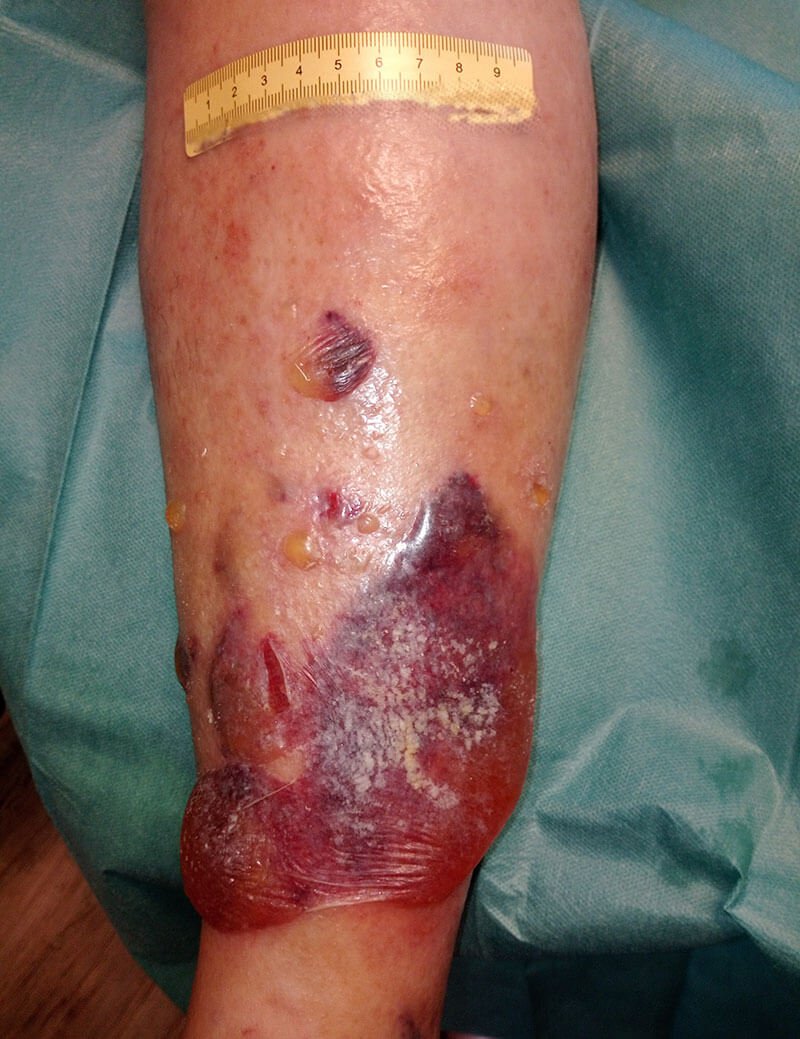

Bild 1 zeigt den Befund bei der Vorstellung des Patienten. Nach Entfernung der sich ablösenden Oberhaut (Bild 2) zeigen sich granulierende Wunden am Unterschenkel. An den Wundrändern sieht man, dass sich im Verlauf vermutlich weiter etwas Oberhaut ablösen wird. Die Unterschenkel sind insgesamt leicht ödematös, das gesamte Hautbild ist sehr gepflegt. Die sich ablösende Oberhaut wird abgetragen und die Umgebungshaut wird mit dünn einmassierter Zinkcreme vor der austretenden Exsudation geschützt.

Die Wundversorgung erfolgt mit einem Wunddistanzgitter und zunächst mit einem Superabsorber. Fixiert wird die Wundauflage mit einem Schlauchverband. Darüber wird ein moderater Kompressionsverband mit Polsterwatte und einer selbsthaftenden Binde ohne Zug angelegt. Dabei muss regelmäßig überprüft werden, dass keine Einschnürungen entstehen und der Verband nicht verrutscht. Da ein Superabsorber eingesetzt wird und keine Infektionszeichen vorliegen, wird der nächste Verbandswechsel 4 Tage später stattfinden.